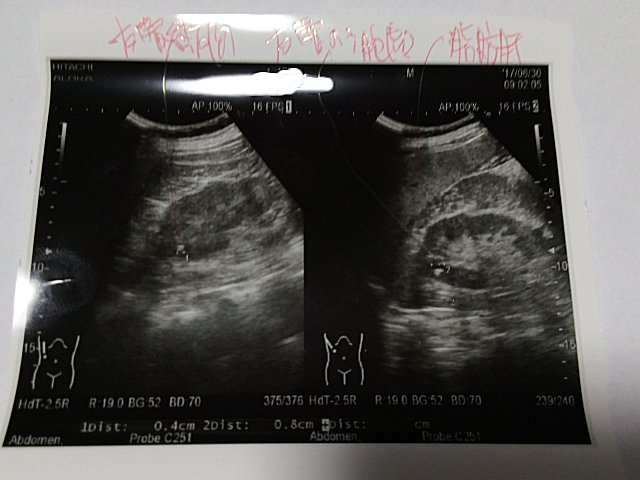

Img_20170701_0113371 右腎臓結石 右腎嚢胞 脂肪肝